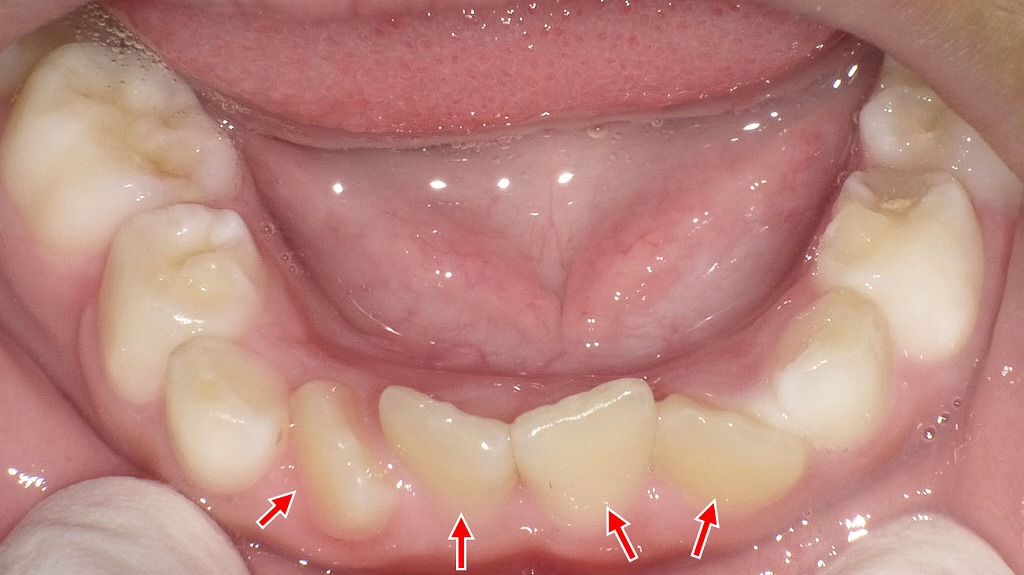

下記の口腔内写真は下顎前歯に**叢生(歯の重なり)**があり、歯間の清掃がやや難しい状態です。プラークがたまりやすく、歯石や歯肉炎の原因になることがあります。